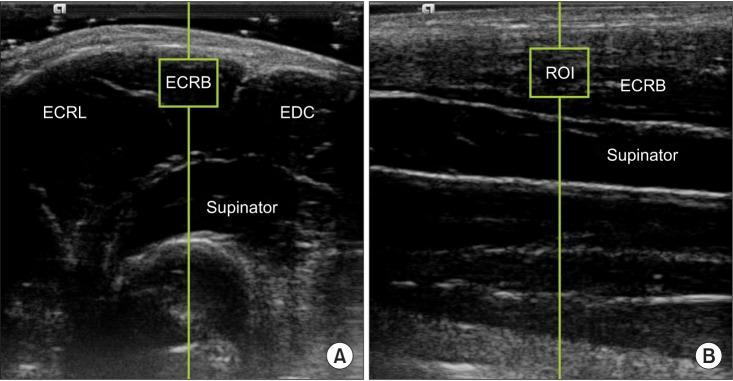

A variety of treatment options suggest that the optimal treatment strategy for lateral elbow tendinopathy (LET) is not known, and further research is needed to discover the most effective treatment for LET. The purpose of the present study was to verify the most effective position of eccentric stretching for the extensor carpi radialis brevis (ECRB) using ultrasonic shear wave elastography.

A total of 20 healthy males participated in this study. Resting position was defined as 90° elbow flexion and neutral position of the forearm and wrist. Elongation of the ECRB was measured for four stretching maneuvers (forearm supination/pronation and wrist extension/flexion) at two elbow angles (90° flexion and full extension). The shear elastic modulus, used as the index of muscle elongation, was computed using ultrasonic shear wave elastography for the eight aforementioned stretching maneuverangle combinations.